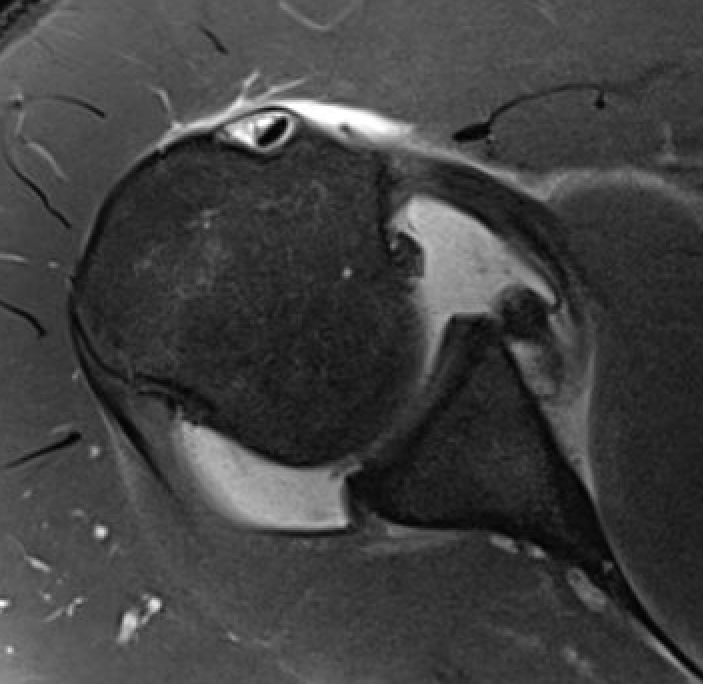

Normal humeral insertion of IGHL on left, HAGL with discontinuity of J sign on right